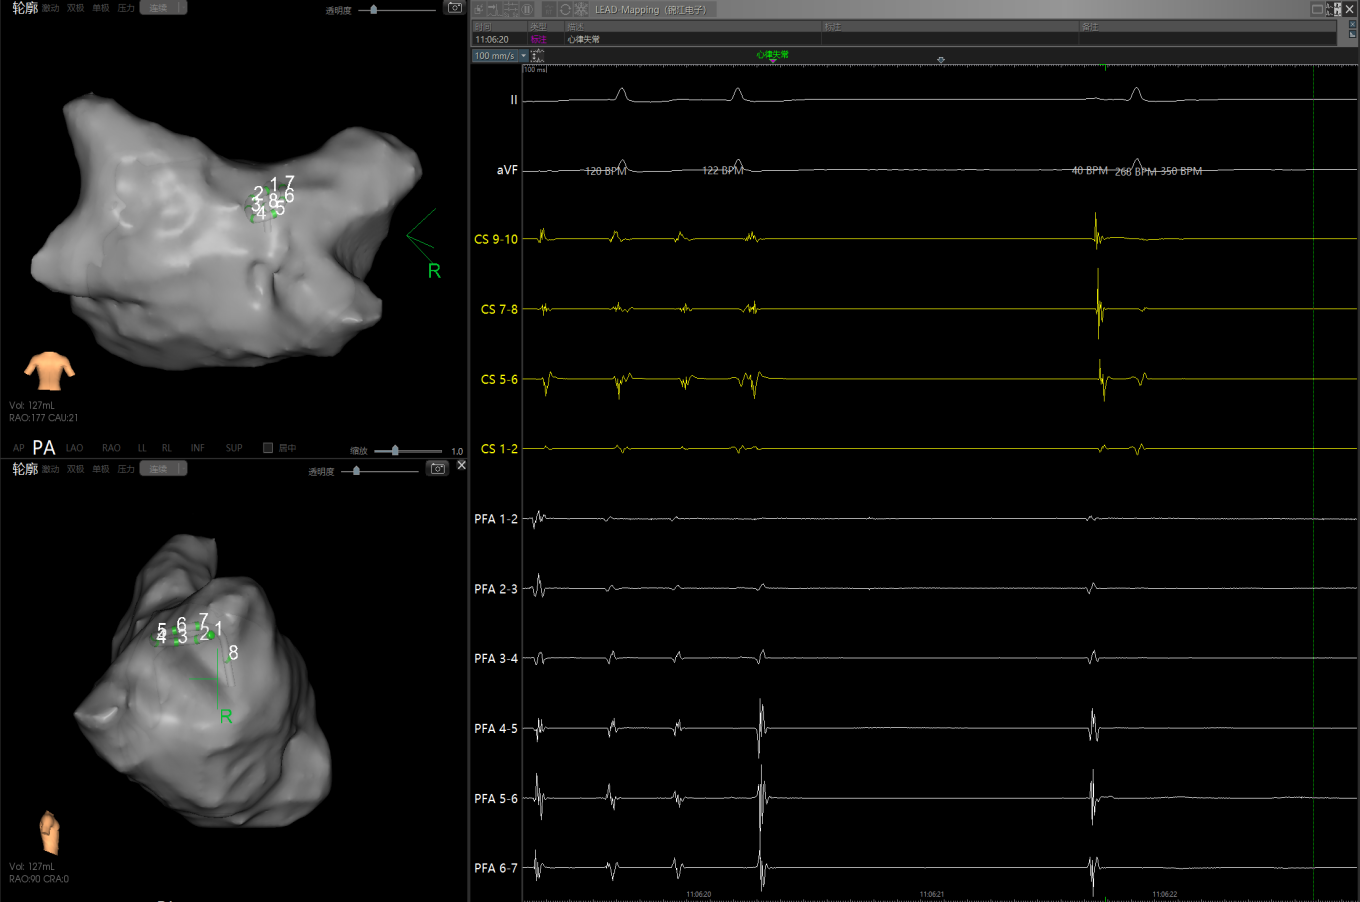

经充分术前评估及准备后,该患者手术在抗心衰药物持续静脉泵入、高流量吸氧支持下及麻醉、护理团队的通力配合下进行,由薛建颖、崔明亮主治医师具体实施。术中通过右侧股静脉送入心腔内超声至右心房,排除左房血栓后成功指导房间隔穿刺,沿可调弯鞘管送入锦江心脏脉冲电场消融导管至左房,构建左房三维解剖模型并行基质标测,标测显示左房基质差,分别行左侧、右侧肺静脉及后壁BOX消融。消融参数:1800v,400ms,400μs,共放电消融140次(消融右肺静脉时转复为窦性心律),验证双肺静脉均隔离。术后重新标测显示所有肺静脉均已急性阻滞,消融效果理想,肺静脉前庭损伤范围也达到了预期的标准,同时心腔内超声监测未见明显心包积液。手术仅用时30分钟,时间明显缩短,手术过程精准高效。术后患者恢复情况良好,维持窦性心律。

图1 患者因心功能差行电复律,窦律无法维持